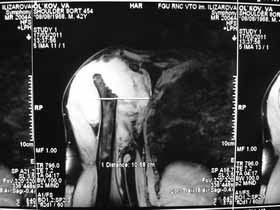

Поэтому желательно выставить все рентгенологические и данные МРТ для сравнения со снимками из статьи.

Думаю, коллеги будут не против увидеть рентген.

Извиняюсь, что-то фотографии сразу не прошли. сейчас исправимся.